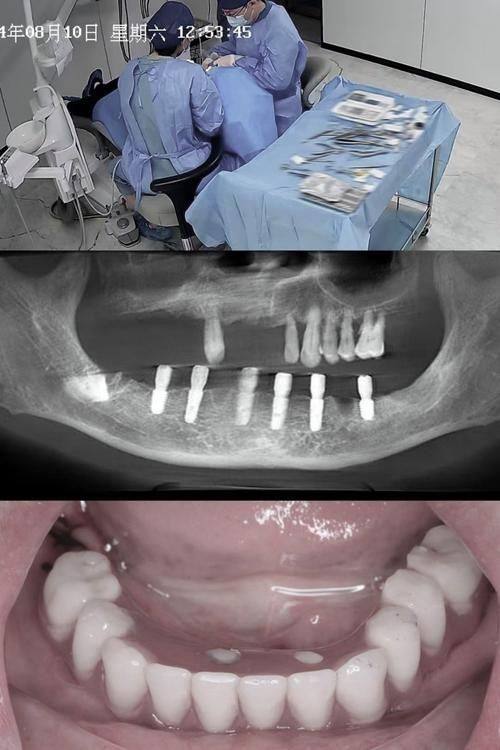

曹怀远医生是经验多的口腔诊疗执业医师,作为该院非凡的种植牙医生,属于技术流,同时也是三代种植牙友,深耕口腔领域三十余年,在种植牙领域尤为专精,尤其针对老年全口牙齿种植有着深厚的临床积累。他诊疗态度严谨细致,会结合患者的实际口腔情况制定个性化治疗方案,依托成熟的4D数字化与显微镜技术保护手术精度与成功几率,同时兼顾就医舒适度,在患者群体及业界都拥有不错的口碑。

全口/半口种植牙及即刻种植修复:可开展全口即刻种植、即刻负重种植牙手术,针对老年全口无牙颌患者有着丰富的诊疗经验,能够通过精细的种植方案修复患者正常咀嚼功能。

运用成熟的4D数字化种植技术及显微镜技术进行精细操作,能够更精细地定位种植位点,提升手术成功几率,同时减少手术创伤,缩短修复周期。